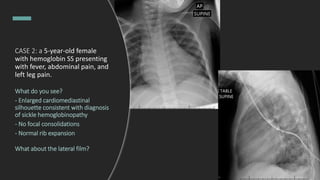

CASE 2: a 5-year-old female with

hemoglobin SS presenting with

fever, abdominal pain, and left leg

pain.

CXR is ordered. What do you see?

- Enlarged cardiomediastinal

silhouette consistent with diagnosis

of sickle hemoglobinopathy

- No focal consolidations

- Normal rib expansion

What about the lateral film?